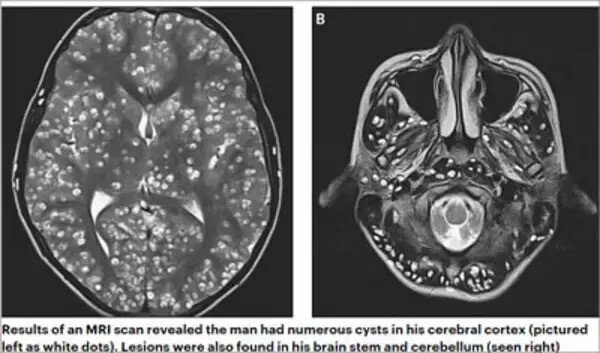

そこでMRI検査を行ったところ、脳の至るところに無数の嚢胞(のうほう)が見つかった。写真を見ると、米粒のような白い影が頭部全体にびっしりと写っているのが素人目にもわかる。

男性は神経嚢虫症とみられ、豚肉に寄生するサナダムシなどの寄生虫の幼虫が、脳の神経系統に侵入し、てんかんを起こしたものと診断された。